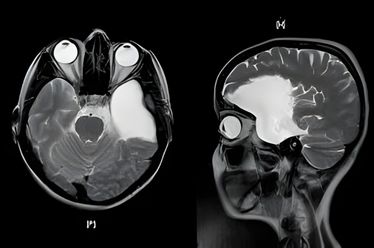

Hidrocefalia de Pressão Normal

O Que é a Hidrocefalia de Pressão Normal (HPN)? A Hidrocefalia de Pressão Normal é uma condição neurológica que afeta […]

Tumores Cerebrais

Entendendo os Tumores Cerebrais Um tumor cerebral é o crescimento anormal de células dentro do crânio. Eles podem ser primários,